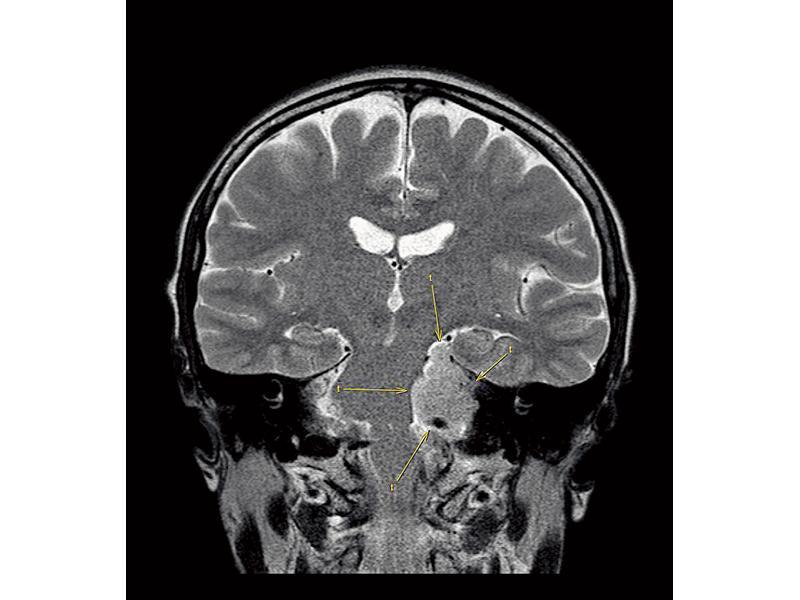

陳淑莊在社交網站上載兩張腦部磁力共振的圖片,顯示

陳淑莊在社交網站上載兩張腦部磁力共振的圖片,顯示腦膜瘤令到腦幹彎曲。她透露為了準備接受刑責,本月4日在一間私家醫院接受身體檢查,上星期三取得報告,指她腦內「有此東西」。在復活節假期前接受磁力共振掃瞄,確診腦內有腦膜瘤。公民黨黨友余若薇的丈夫、腦科醫生胡健維考慮到她持續出現不同程度的病徵,包括頭暈及面部麻痹等,故建議必須盡快接受手術。她稱要待開腦後才知道腫瘤是良性還是惡性,之後有機會要接受放射治療。